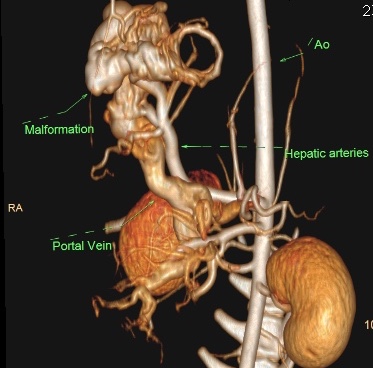

Для эмболизации артериовенозной мальформации печени (рис. 4) у 5-месячной собаки весом 2,7 кг автор статьи использовал спирали, а также коллагеновую губку и клей (3M Vetbond). Сосудистый доступ осуществлялся через бедренную артерию, в которую был установлен интродьюсер 4 Fr (рис. 5). Катетеризация печеночной артерии проводилась катетером Cobra, 4 Fr (рис 6.) В трех наиболее крупных ветвях приносящих артерий были размещены спирали, однако сильный ток крови в сосудах «гнезда» после размещения спиралей сохранялся. Из коллагеновой губки, контрастного вещества («Ультравист») и физраствора была приготовлена смесь в объеме 1,0 мл, которая была введена через катетер 4 Fr, размещенный в области бифуркации приносящих артерий «гнезда». Это снизило риск миграции клея в портальную вену и нецелевой эмболизации. После этого по катетеру был введен клей 3M Vetbond. По окончании манипуляции в сосудах «гнезда» мальформации не отмечалось наличия тока крови.

Диагностика печеночных АВМ осуществляется с применением КТ-ангиографии, выявляющей сосудистую сеть (или «гнездо»), образованную ветвями приносящей печеночной, гастродуоденальной, левой желудочной и другими артериями, через которую происходит слияние с воротной веной (рис. 3). Артериальная фаза является самой важной в идентификации приносящих ветвей артериовенозной мальформации. АВМ имеют тенденцию изменяться со временем, в связи с этим КТ-ангиографию рекомендуют проводить как можно ближе к дате планируемого хирургического вмешательства.